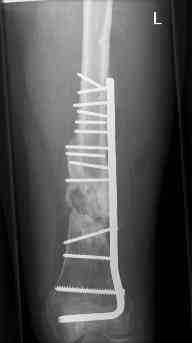

16 yr old boy, high energy motorcycle trauma trauma in July 2005 with:

- hip dislocation + acetabular fracture L

- distal femoral fracture L

- tibial shaft fracture L

- metatarsal fractures L

july 05: LISS femur, LCP plate tibia, double recon. plate post. acetabulum

oct 05: cancellous bone graft femur

aug 06: blade plate + bone graft